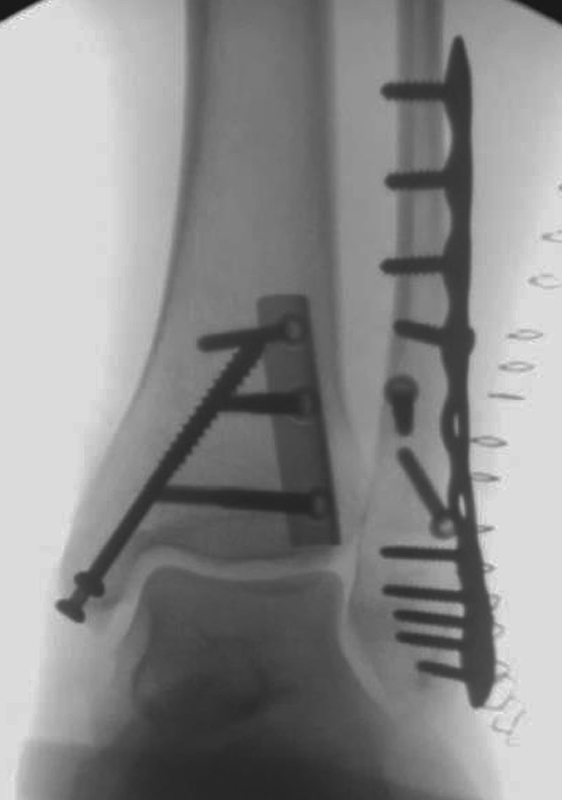

Die Versorgung von AO 44-B Frakturen erfolgt über einen längsverlaufenden lateralen Zugang. In der Regel gelingt eine suffiziente Stabilisierung mittels interfragmentärer Zugschraube (bei langem Frakturverlauf ggf. 2 Zugschrauben) und einer zusätzlichen Neutralisationsplatte (Abbildung 9 & 10).

Bei multifragmentären Frakturen (AO 44-B2.3) oder bei schlechter Knochenqualität sollte die Versorgung mittels winkelstabiler Plattenosteosynthese erwogen werden (Abbildung 11 & 12).

Frakturen vom Typ AO 44-C werden in der Regel mittels interfragmentärer Zugschraube und Neutralisations-Plattenosteosynthese versorgt. Die Versorgung von Frakturen mit metaphysärer Trümmerzone (AO 44-C2) ist mitunter anspruchsvoll. Entscheidend ist die Wiederherstellung der korrekten Länge und Rotation der Fibula. Die Verwendung von winkelstabilen Implantaten bietet hier eine höhere Stabilität. Bei Typ C Verletzungen liegt definitionsgemäß eine Syndesmoseninsuffizienz vor, die entsprechend versorgt wird (siehe Abschnitt Syndesmoseninsuffizienz). Bei hohen Fibulafrakturen (AO 44-C3, Maisonneuve-Frakturen) steht die Versorgung der Syndesmoseninstabilität im Vordergrund. Eine zusätzliche Versorgung der proximalen Fibulafraktur ist nicht erforderlich.

Gardner et al. konnten beispielsweise zeigen, dass die offene anatomische Reposition der Tibiahinterkante der Stabilisierung mittels Stellschraube überlegen war und gleichzeitig mit einer geringeren Rate an postoperativen Fehlstellungen der Fibula in der CT-Kontrolle einherging 2728. Aus Sicht der Autoren ist prinzipiell die Stabilisierung über eine direkte Reposition indiziert, wenn die Größe des Fragmentes dies erlaubt. Bei gleichzeitigem Vorliegen einer Fraktur des lateralen und/oder medialen Malleolus sollte zunächst die Versorgung der des Tibiahinterkantenfragments erfolgen. Dies erlaubt die radiologische Kontrolle der Reposition und Osteosynthese-Lage, welche durch eine zuvor aufgebrachte Fibula-Platte häufig erschwert ist 29. Dafür werden die Patienten in Seitenlage gelagert. Dies erlaubt die direkte Versorgung der posterioren Malleolusfraktur über einen posterolateralen Zugang 30. Das sehr kräftige Periost wird im Frakturverlauf inzidiert und aus den Frakturspalt entfernt, so kann eine anatomische Reposition erfolgen. Entsprechend der Fragmentgröße erfolgt entweder die Versorgung mittels Drittelrohrplatte in Antiglide-Technik oder eine Zugschraubenosteosynthese. Die Versorgung der Fibula-Fraktur gelingt über den gleichen Zugang. Zur Versorgung des medialen Malleolus wird der Patient auf den Rücken umgelagert. Dies kann bei entsprechender Vorbereitung ohne erneutes steriles Abdecken erfolgen. Durch dieses Vorgehen konnte im eigenen Kollektiv die Notwendigkeit einer Stabilisierung der Syndesmose mit Stellschraube/Tight Rope deutlich reduziert werden.